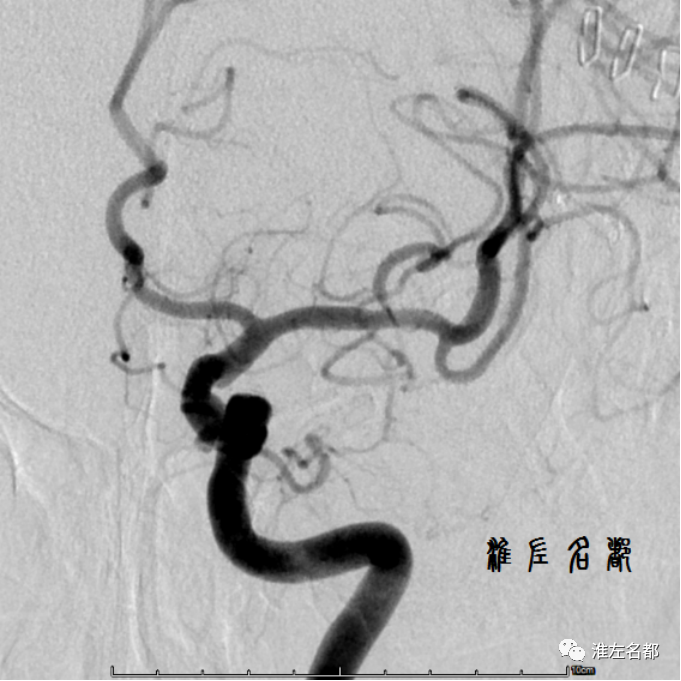

伴随科技发展,近半个世纪以来,多种先进技术,尤其是血管影像技术,被应用于脑血管病变的诊断评估,极大促进了该领域的发展。目前常规应用于脑血管病变评估的影像技术包括:DSA、CTA和MRA,这些技术主要通过显示血管腔的异常进行血管病变的评估,如狭窄、闭塞、动脉瘤、血管畸形等病变,其中以DSA的诊断准确性最高,常被奉为“金标准”,缺点是有创操作,有潜在风险。

回过头来,我们发现前述的几种常用血管影像技术得到的是血管壁病变的继发管腔异常信息,是不完整的间接表现,不同病因可出现相似的管腔异常表现。因此,很多情况下,这些常规血管影像检查结果因缺少典型表现,给诊断带来困扰,尤其是管径细小的颅内血管病变。